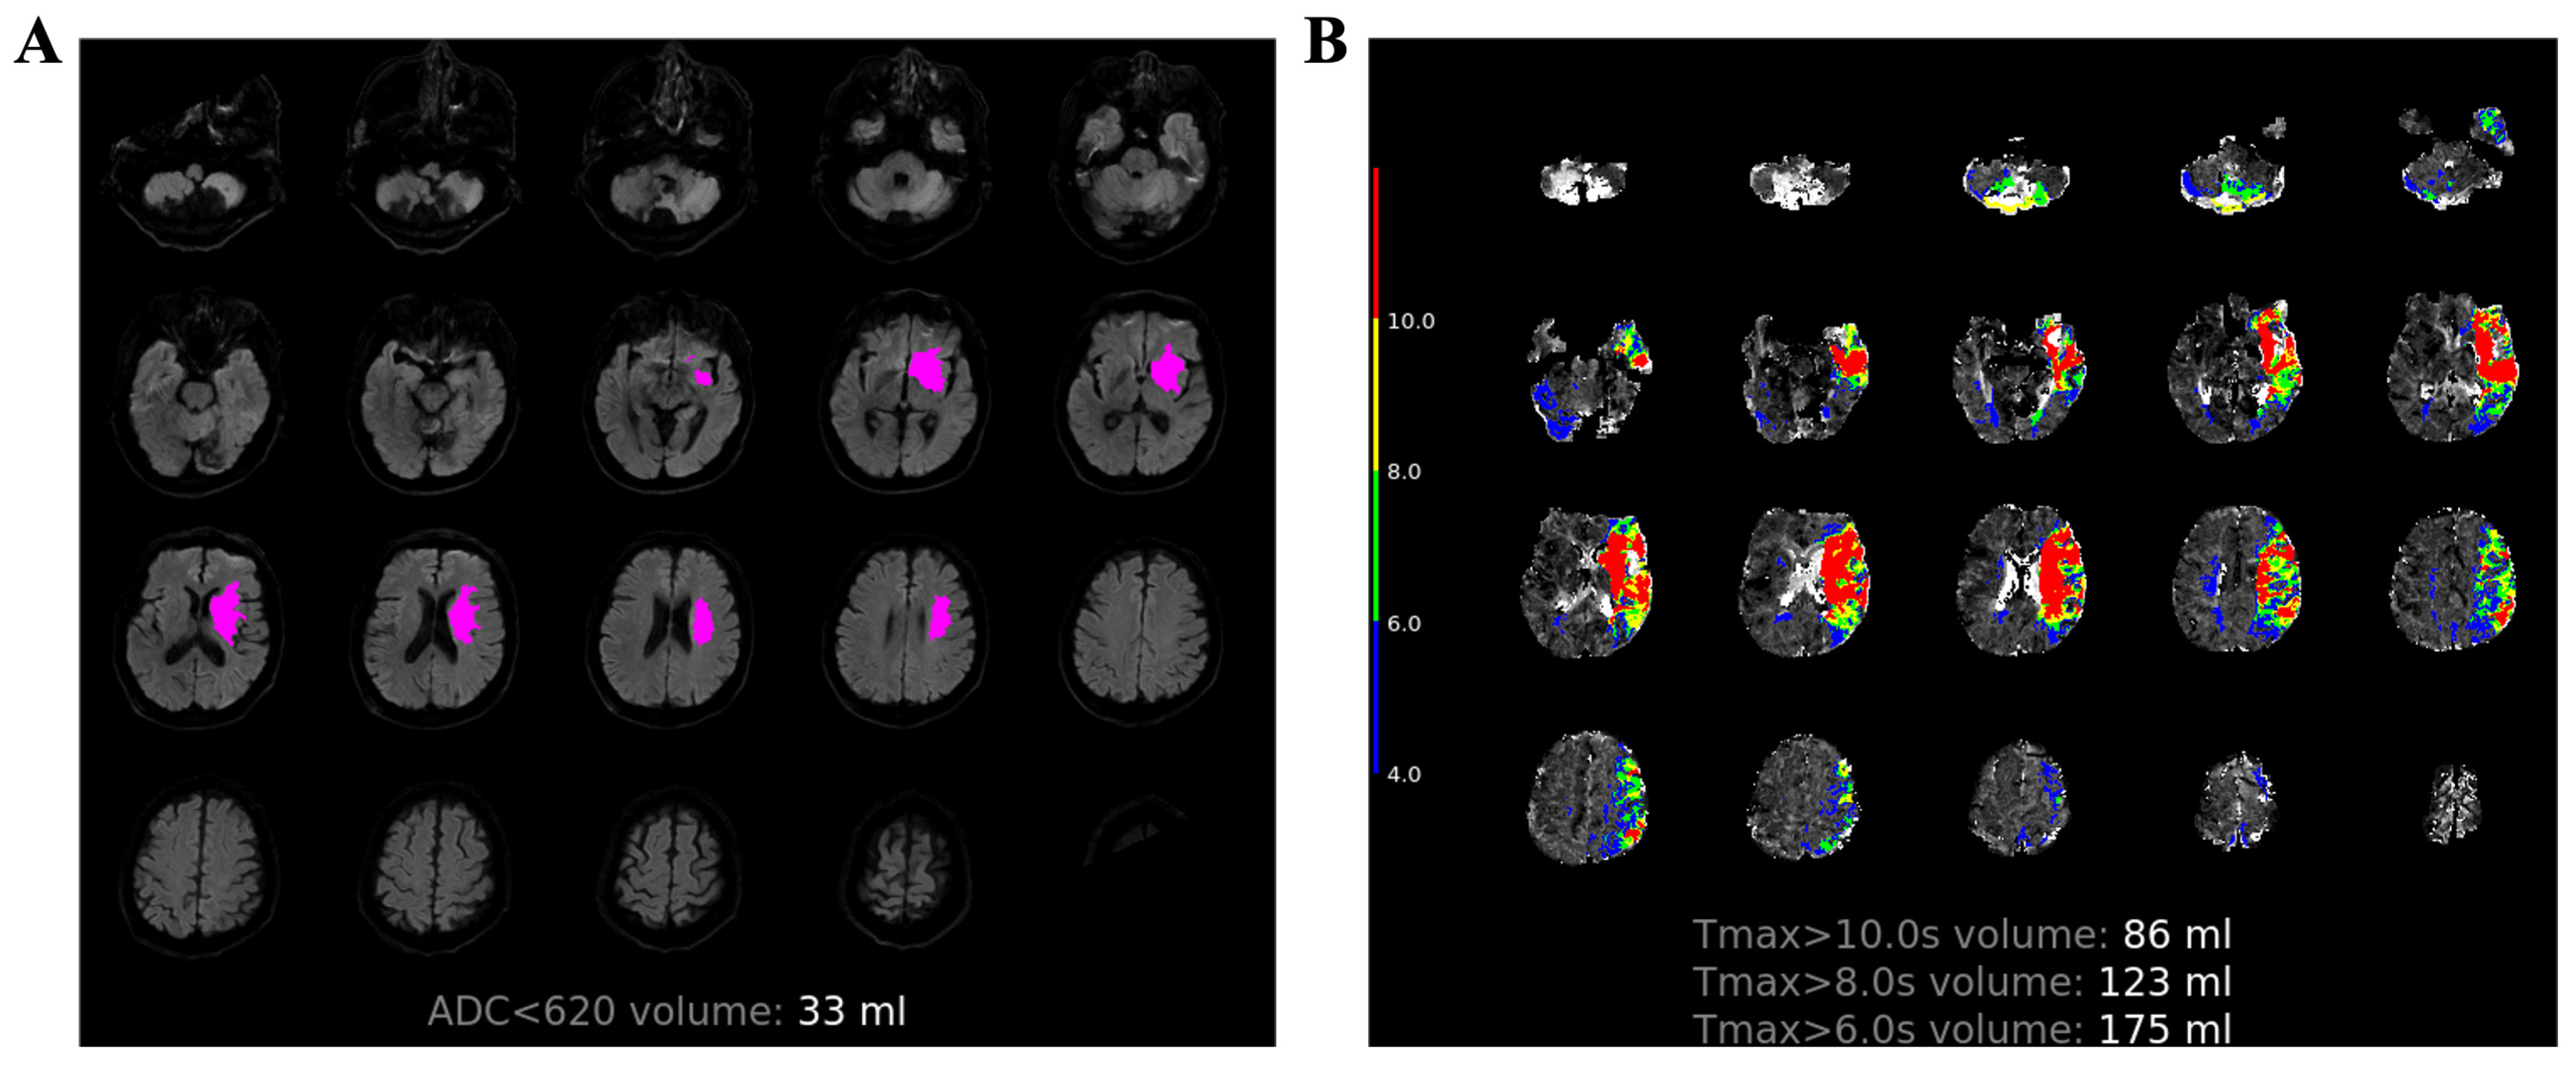

2.2. MR Protocol

2.3. Image Process